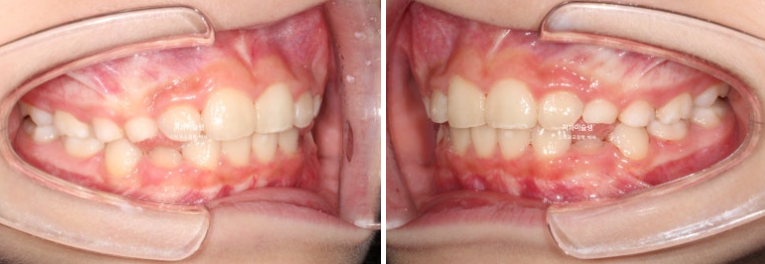

24.05

과개교합은 개선되었고 측절치 나올 공간을 악궁확장으로 미리 벌려줬기 때문에 측절치는 잘 내려왔습니다.

중심선 불일치 개선과 송곳니 나올 공간을 좀 더 확보하기ㅏ 위해서 추가장치 제작에 들어갑니다.

추가장치 갯수는 19개 입니다.

24.08

중심선은 잘 맞아졌고 과개교합은 더 개선이 되었습니다.